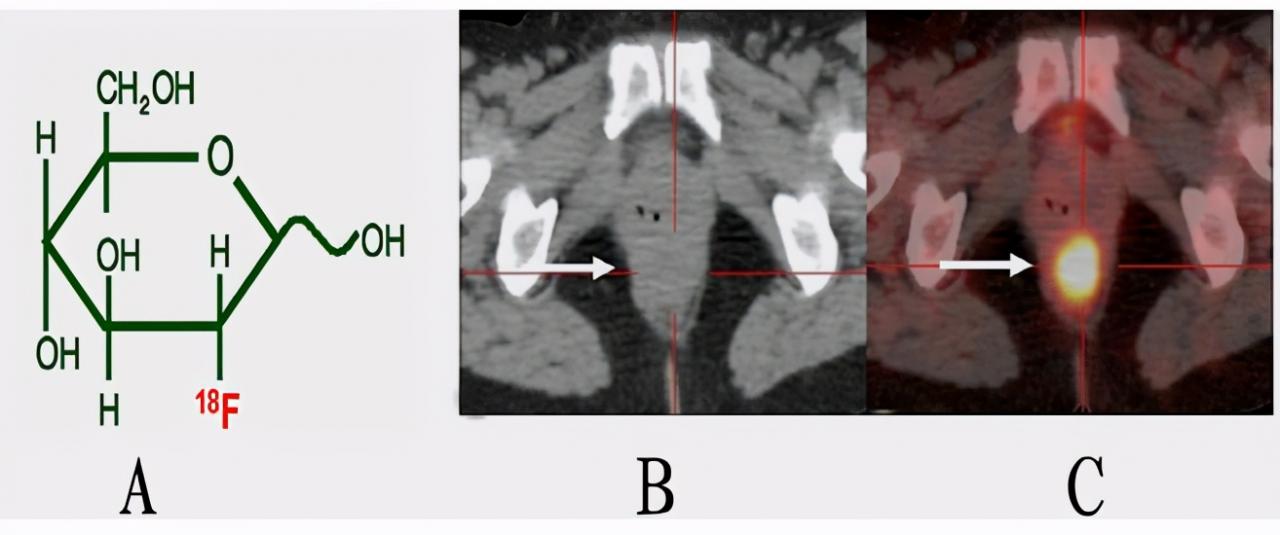

转载自 傅传刚主编《大肠癌100问》PET-CT是什么?PET-CT有哪些优点和缺点?PET-CT是什么?PET的全称为正...